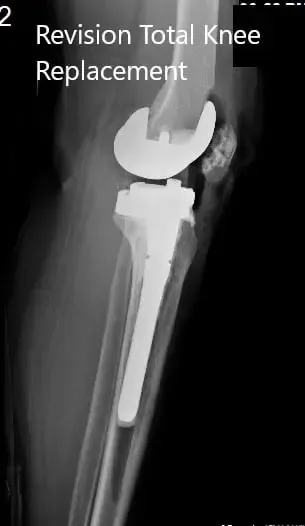

Radiografía postoperatoria que muestra las vistas lateral y anteroposterior de la rodilla derecha.